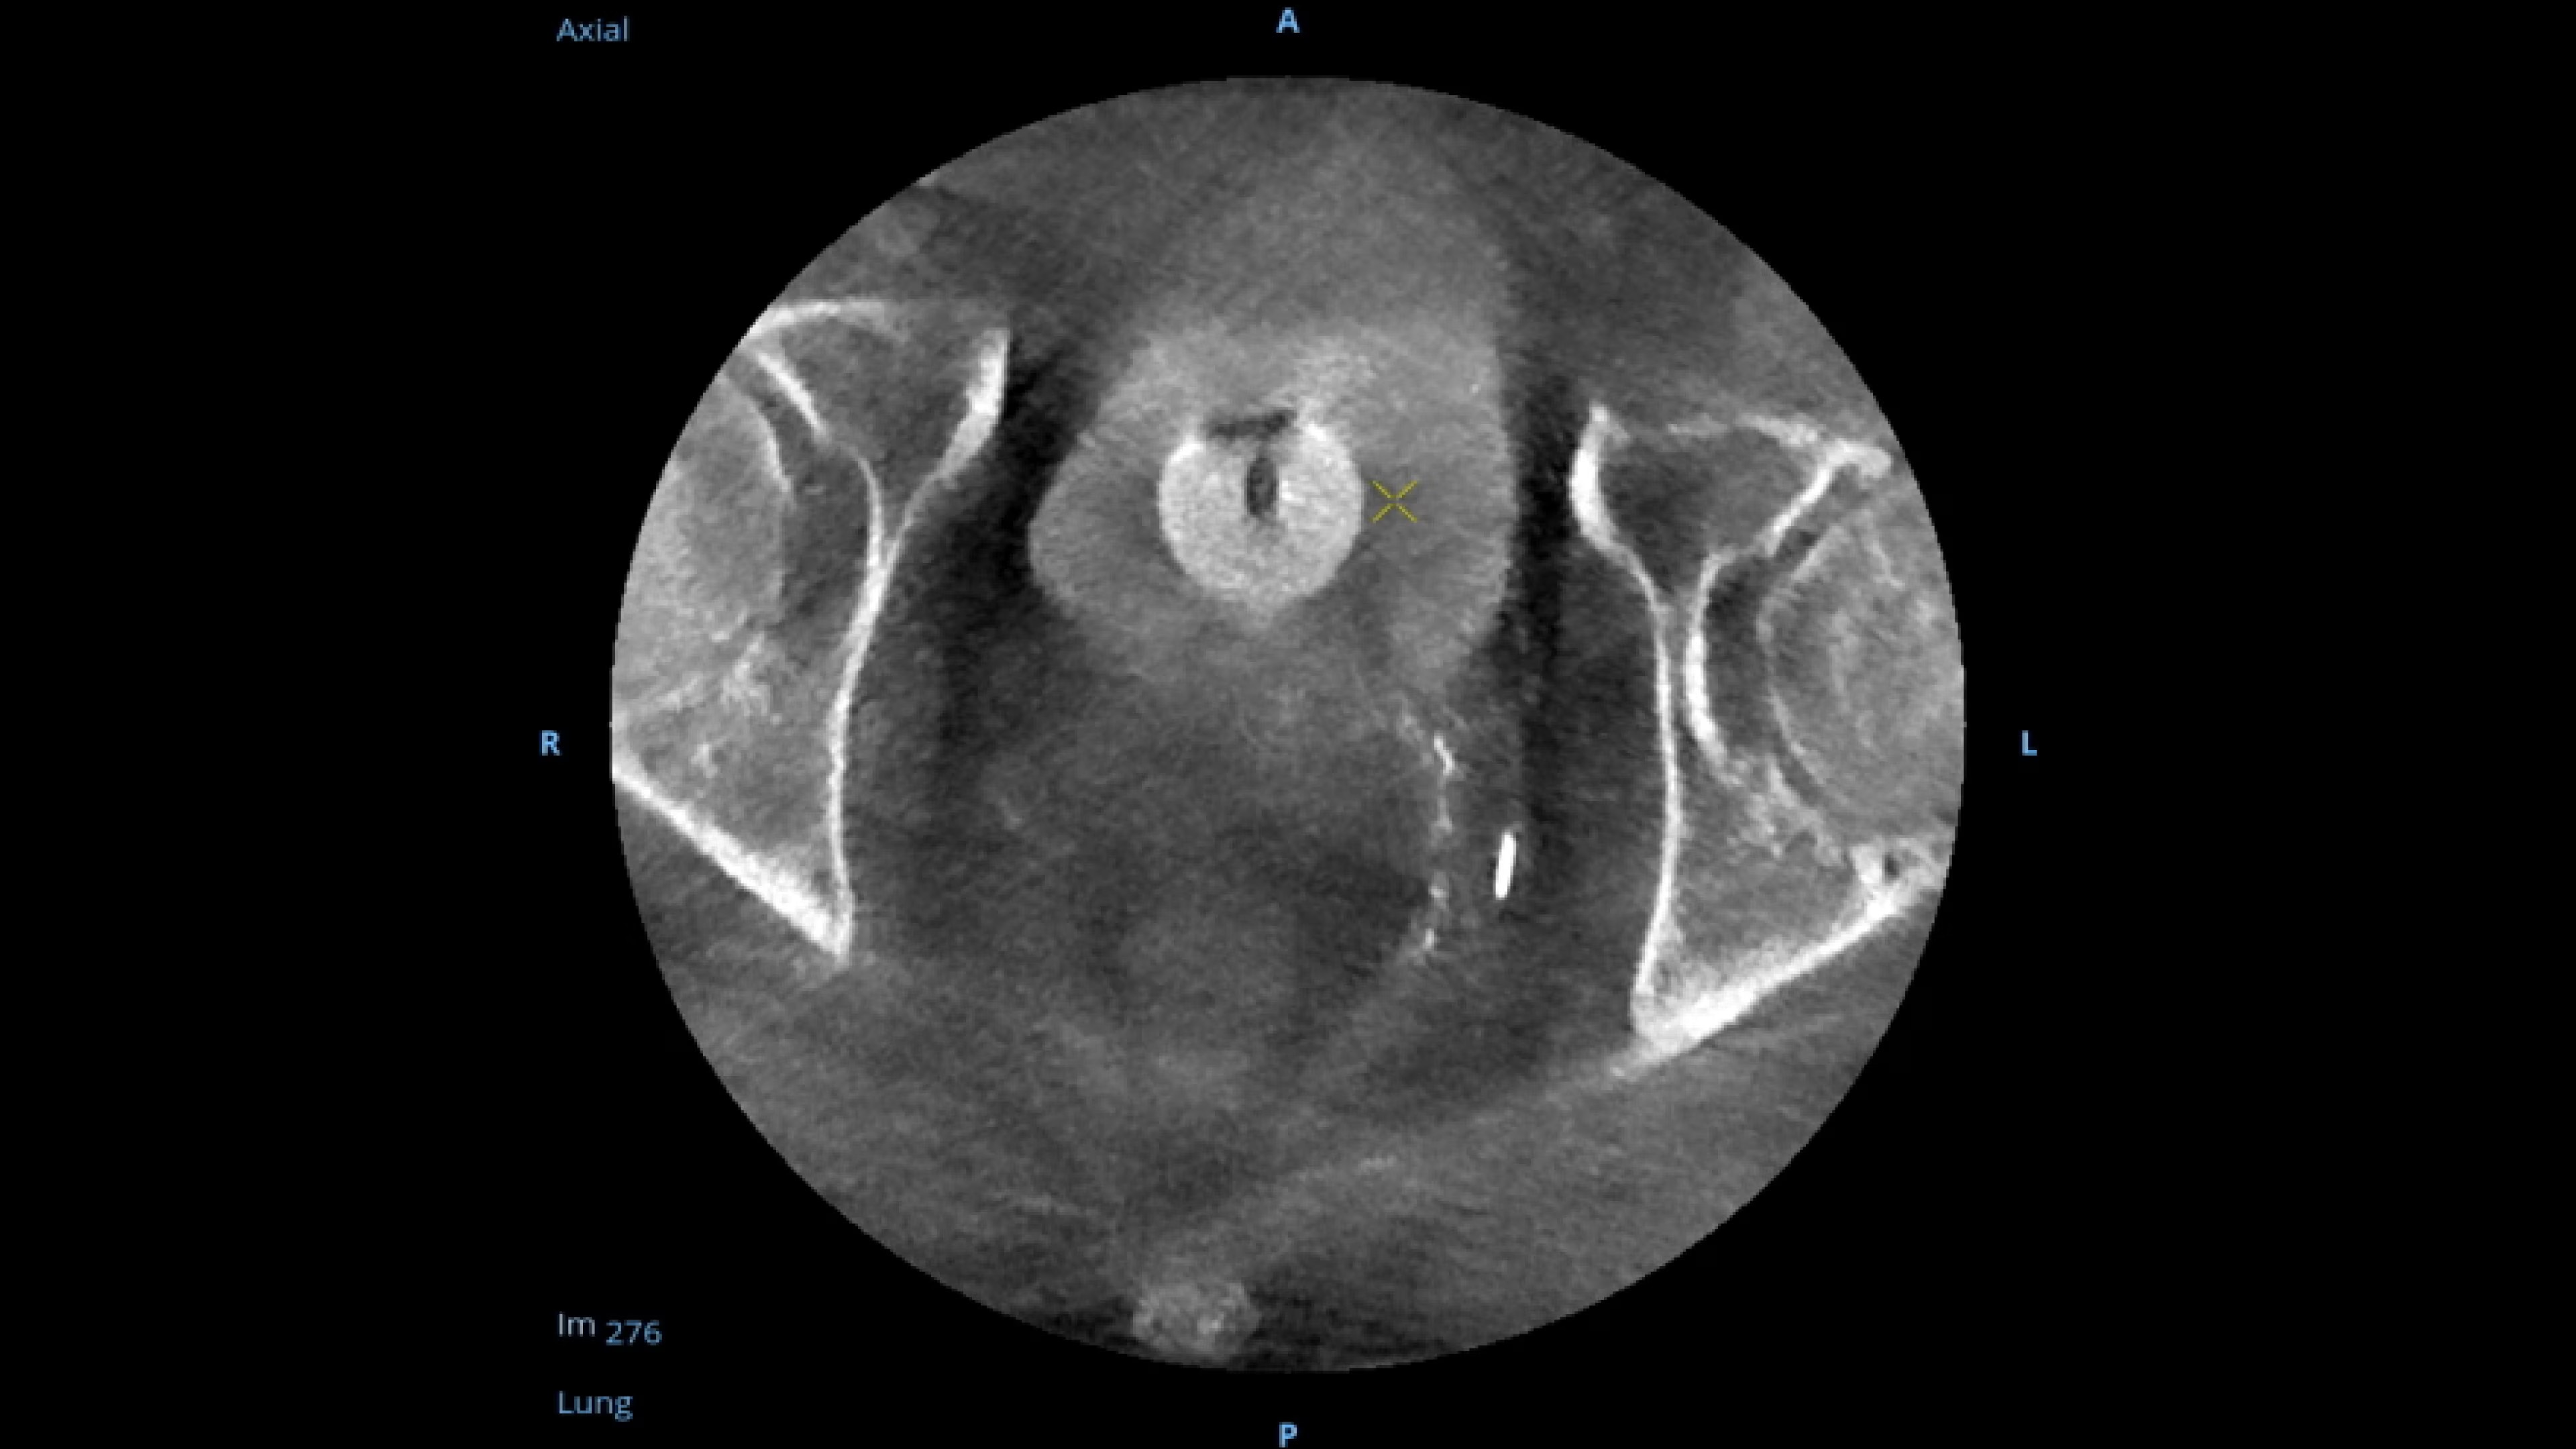

See 0.014” guidewires in chest and abdomen region or 0.008” guidewires in peripheral vascular on a large 4K display.

Experience fixed room-like images with eNR (enhanced Noise Reduction), an advanced software algorithm that automatically reduces image noise by 30%* for an equivalent appearance of

30 kW power.